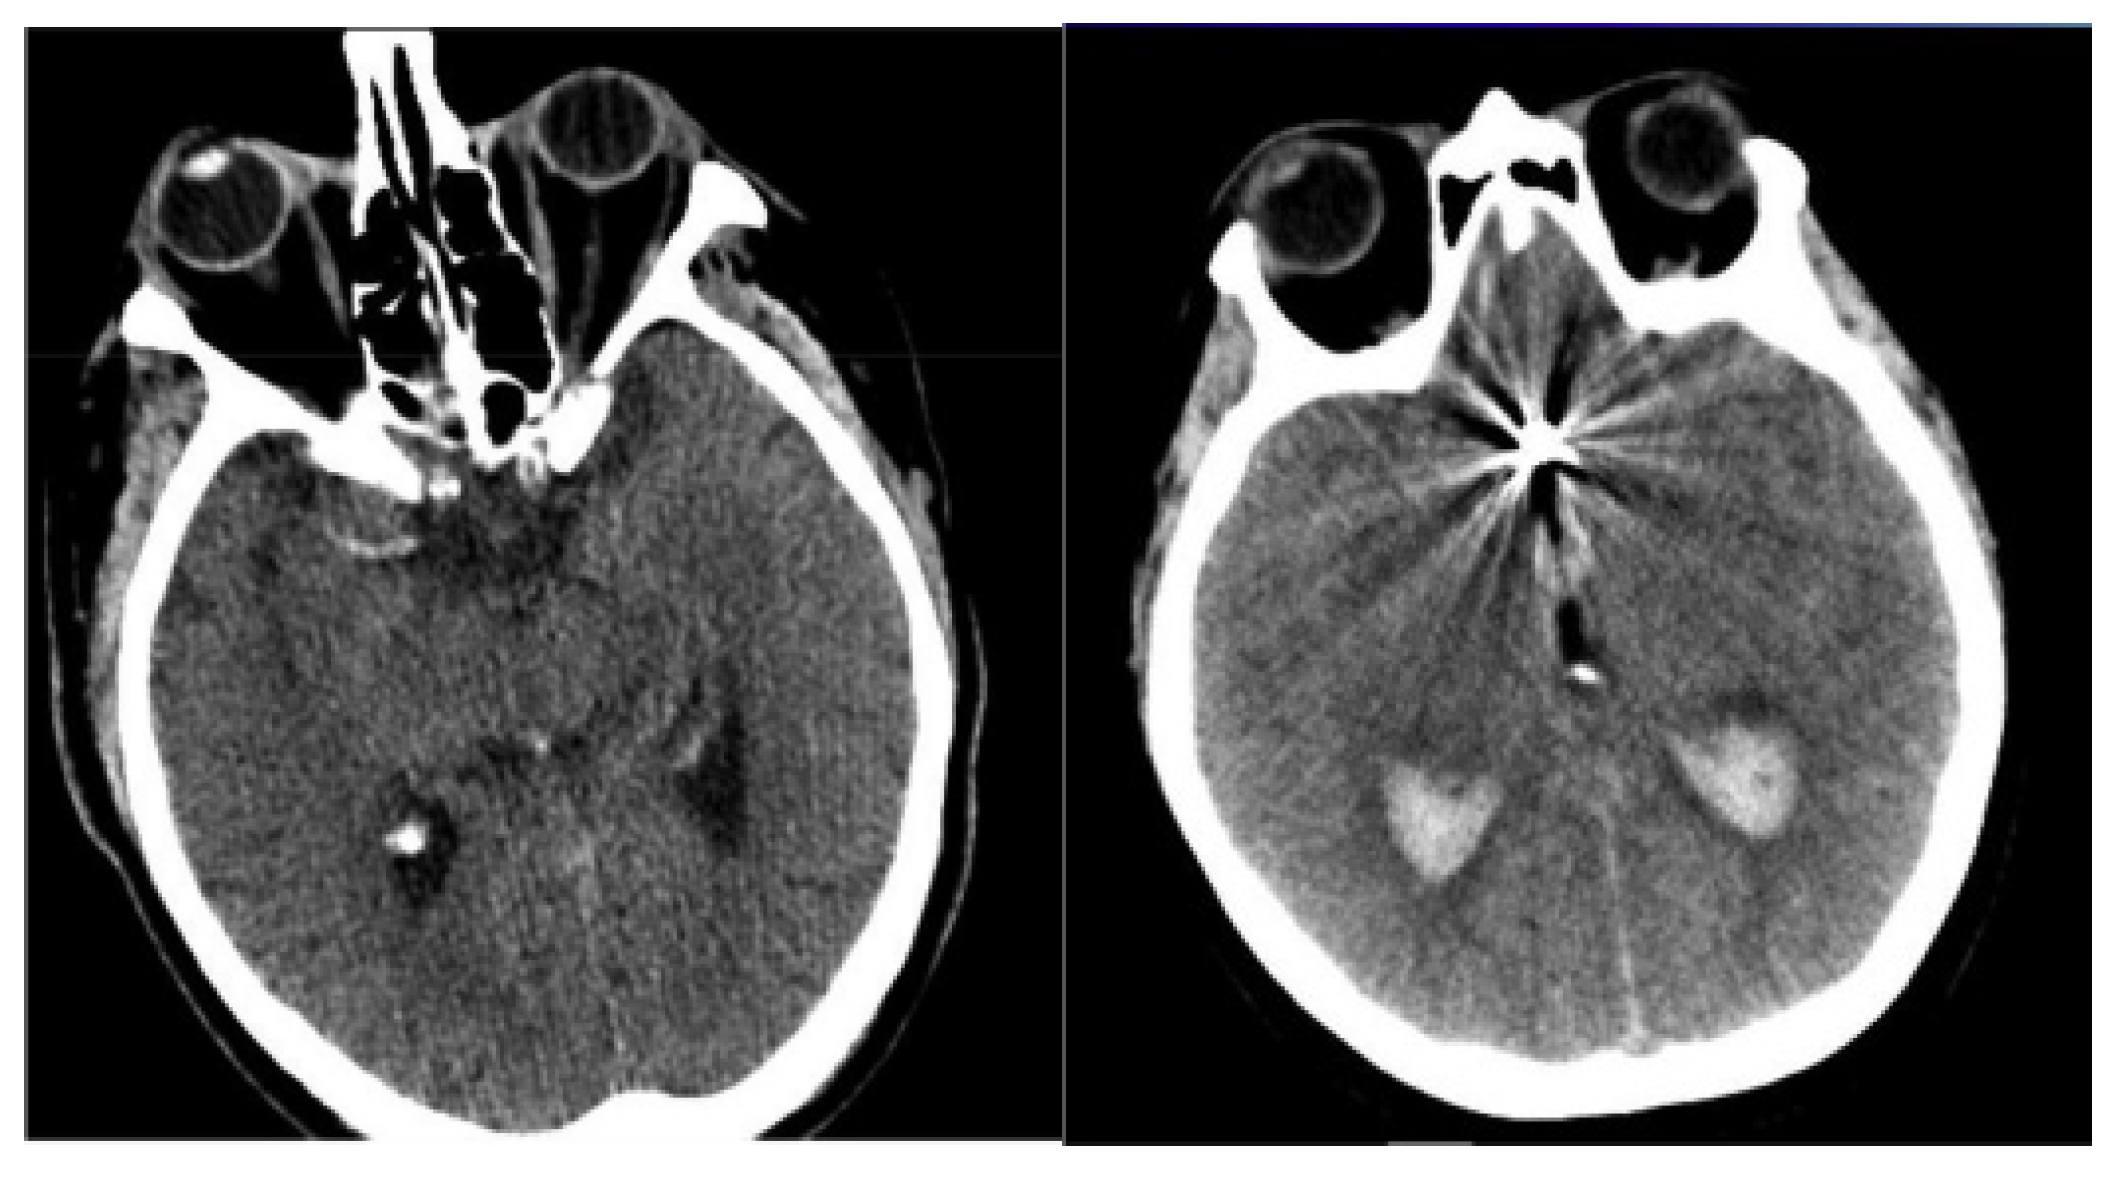

- Finally, determine the differences in orientation and intensity of the pixels and using Equations (3) and (4). The sample-segmented images are graphically presented in Figure 3, where the red area denotes the segmented portions.